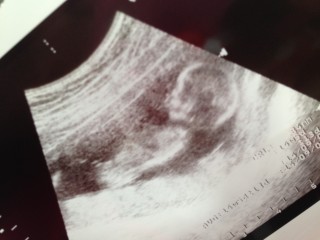

始めて動いてる我が子をみました! 先生にも、かなり動いてるねと言われました(笑) 骨格もハッキリしてて順調だそうです! つわりがまだひどく、ケトンがでてしまったので点滴をしてきましたー… 早くつわり終わらないかなぁ? どうやら亜鉛サプリが体に合わないかららしく、今日からやめてと先生に言われちゃいました(^_^;)

CRL80.2㎜ BPD20.5㎜

今回から経腹エコーでした!

2週間前の検診からきなり倍近く大きく成長していてびっくり!

お顔が骸骨見たいだけどとっても可愛い♡